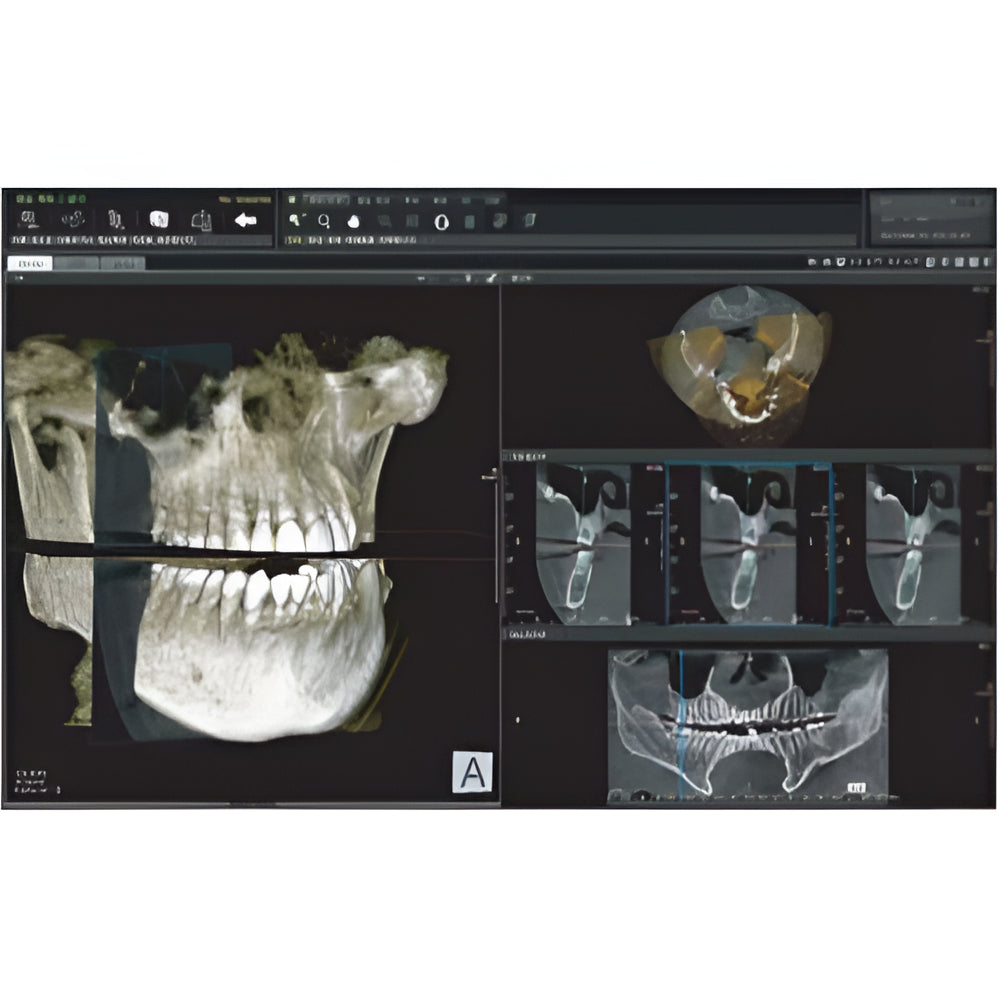

Papaya uses the CdTe sensor, which improves image quality while keeping radiation exposure to a minimum. The CdTe (Cadimium telluride) sensor overcomes the limitations of a CMOS sensor to always produce high quality images.

- 3D imaging software

- Field Of View: 4x5, 7x7, 8x8, 14x8, 14x14

- Multi-FOV selection

- 7.7 sec fast scan for 3D image

- Large FOV